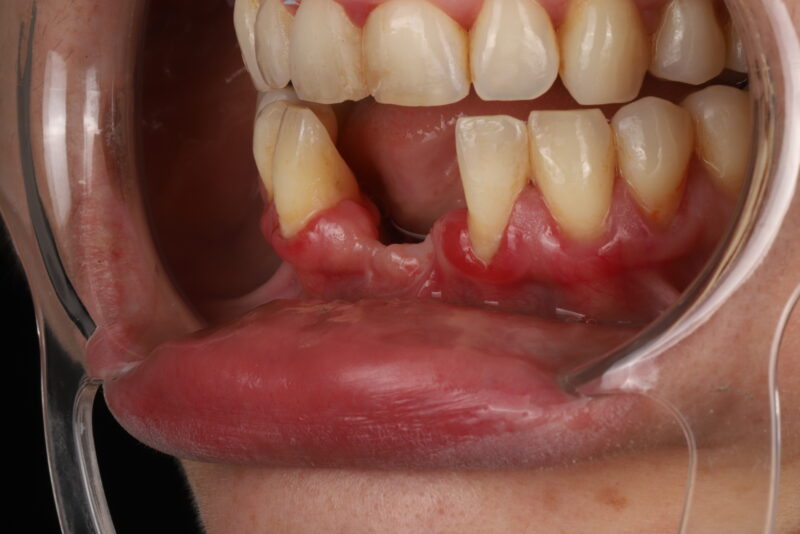

• intraoral pic

• I would remove them both and start over. The only way I’d restore 3 is if it was aware that it had less than 5 year prognosis. The issue was tissue thickness which was less than 2mm thick in all dimensions. I would just be honest with pt that their bone didn’t heal well and you’re concerned about long term prognosis. If they were hell bent I…

Read more